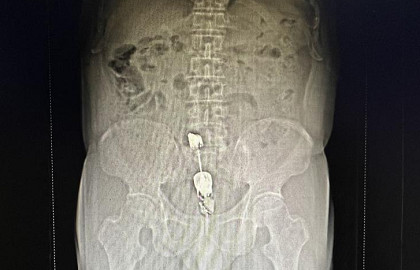

- 【医院科普】太后悔!切莫忽视!一小伙坐着轮椅被推进省人民医院